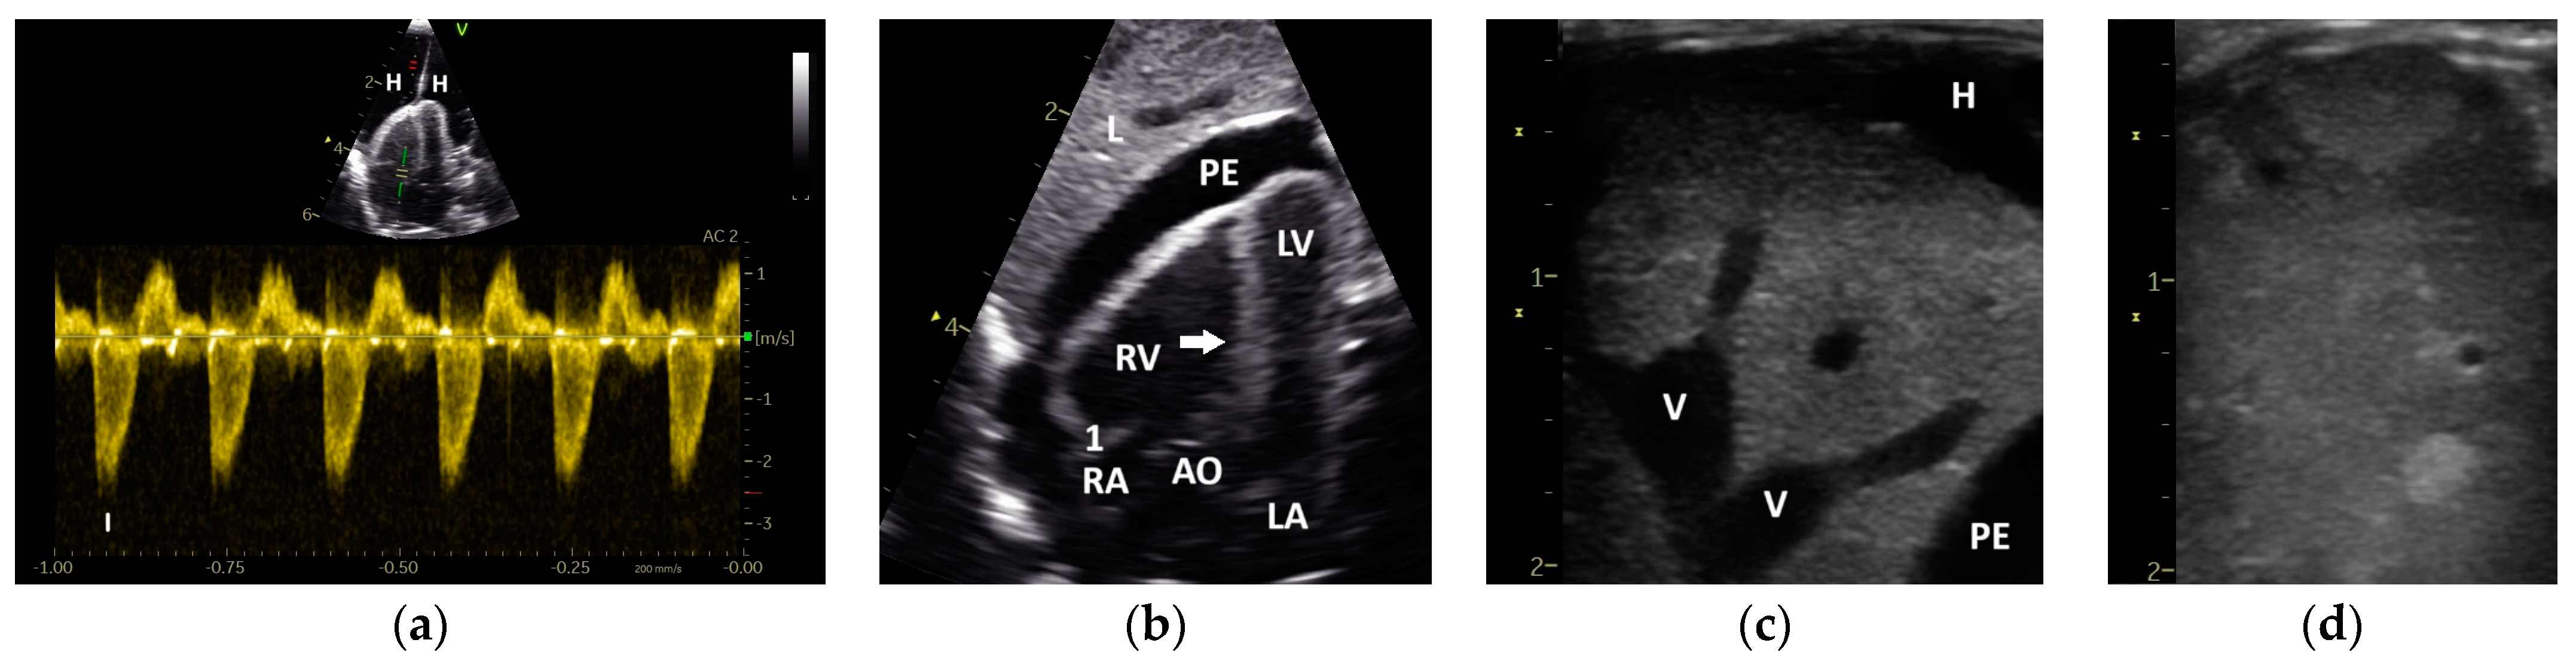

3. Results

3.1. Shape of PAFP and AOFP of Grey Parrots

3.2. The Influence of Heart Failure on the Shape of the PAFP and AOFP

3.5. Correlation of the Pulmonary and Aortic Blood Flow Profiles with Different Heart Diameters